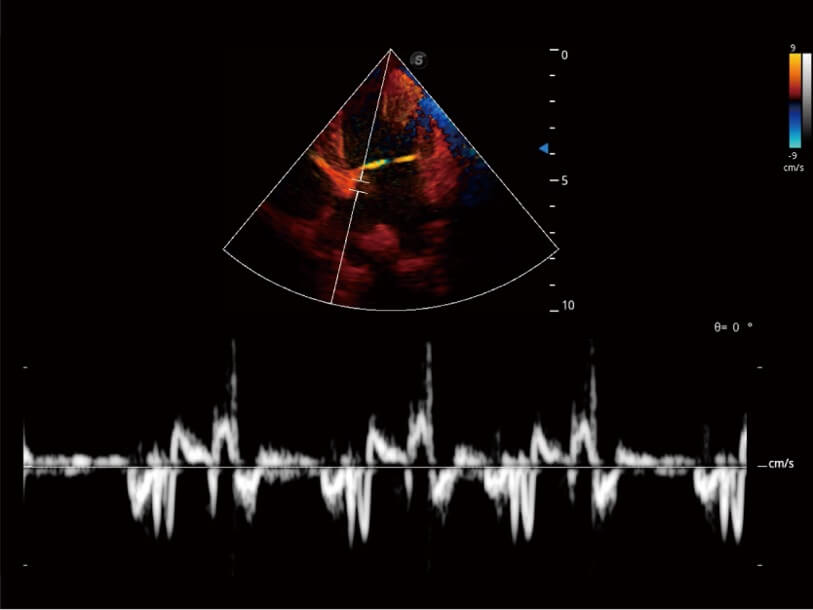

Ausgestattet mit dem gesamten Sortiment an Phased-Array-Schallköpfen von SonoScape (S1-5, 7P-A, 8P1), hochentwickelter Verarbeitungstechnologie und modernsten kardiologischen Tools bietet die ProPet-Serie Tierärzten eine umfassende ABklärung der Herz- und Myokardfunktionen.

Nutzt myokardiale Doppler-Frequenzverschiebungen zur Quantifizierung der myokardialen Gewebebewegung, wobei Rot und Blau die unterschiedlichen Bewegungsrichtungen der Herzwände darstellen. Durch die Kombination von TDI und PW lässt sich die Bewegungsbahn der Myokardwand besser erfassen.